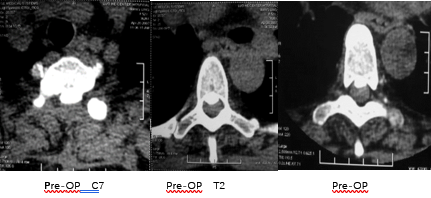

术前影像学检查

MRI: 后纵韧带骨化,尤其T1/T2水平存在巨大的 骨块压迫,C6-T1全椎板切除术后,T1-T2脊髓前方仍存在压迫,相应脊髓变细。

CT: 后纵韧带骨化,T1~2 脊髓前方存在骨化块的压迫。

影像学检查:T1~2 脊髓前方骨化块压迫